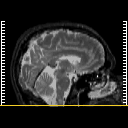

MR Study #5, March 10, 1991 -- Slice #0

[Home][Help][Clinical][Tour 1][Tour 2] Slice 0